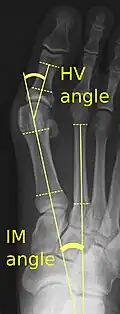

X-ray showing measurements of HV and IM angles of hallux valgus.

Bunions can be diagnosed and analyzed with a simple x-ray, which should be taken with the weight on the foot.[10] The hallux valgus angle (HVA) is the angle between the long axes of the proximal phalanx and the first metatarsal bone of the big toe. It is considered abnormal if greater than 15–18°.[11] The following HV angles can also be used to grade the severity of hallux valgus:[12]

• Mild: 15–20°

• Moderate: 21–39°

• Severe: ≥ 40°

The intermetatarsal angle (IMA) is the angle between the longitudinal axes of the first and second metatarsal bones, and is normally less than 9°.[11] The IM angle can also grade the severity of hallux valgus as:[12]

• Mild: 9–11°

• Moderate: 12–17°

• Severe: ≥ 18°